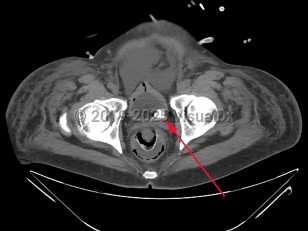

Urinary bladder calculus

When urine is chronically retained in the bladder, any nidus, such as a small fragment of a stone passed from the ureter, a bladder diverticulum, or a foreign body such as a ureteral stent or Foley catheter, can serve as a site for the precipitation and deposition of uric acid. In most retrospective studies of bladder stone composition, nearly all stones (as many as 80%) are entirely composed of uric acid, and most of the remainder contain a substantial portion of uric acid. Interestingly, neither gout or hyperuricemia appear to be contributory factors in the formation of bladder calculi. This is qualitatively different than nephrolithiasis, which in the United States is primarily due to calcium oxalate or calcium phosphate stones.

Infrequently, stones may be formed from calcium oxalate, calcium phosphate, ammonium urate, cystine, or struvite (calcium-ammonium-magnesium phosphate or "triple phosphate"). Stones composed of struvite are almost always associated with chronic UTI and colonization with Proteus. An additional provoking factor in bladder stone formation is thought to be any condition that causes urothelial inflammation such as UTI and bacteriuria or urothelial dysplasia.